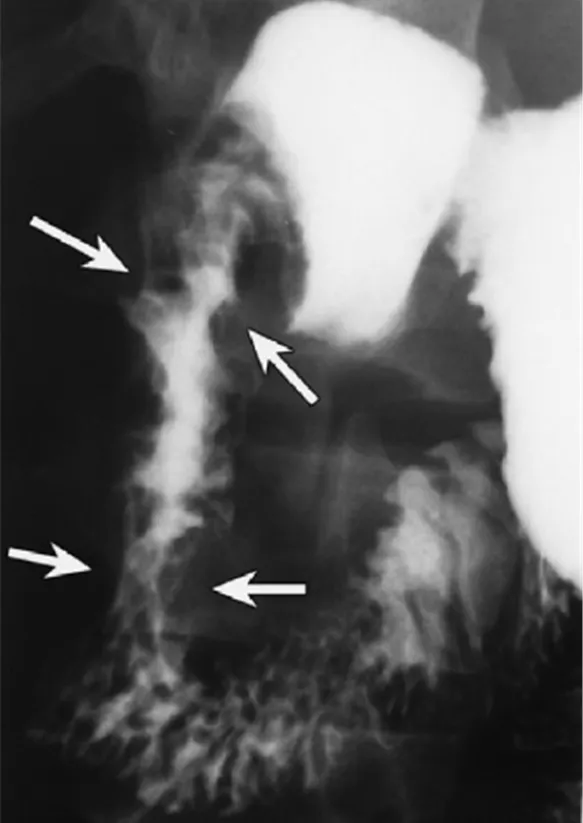

건강한 28세 여성이 자전거 사고 후 우측 상복부 통증을 호소하며 병원에 도착했다. 우측 상복부에 멍이 들어 있었고, 혈액 검사 결과는 정상 범위였다. 사고 후 사흘째, 환자는 담즙성 구토를 시작하여 상부 위장관 조영술과 복부 CT를 실시하였다. 적절한 치료방법은 무엇인가?

• 담즙성 구토를 호소하는 환자에서 위장관조영술의 filling defect가 관찰되어 폐색이 구토의 원인으로 보인다.

• 기저질환 없는 젊은 환자의 외상력과 우상복부 멍이 있는 점을 고려했을 때 외상으로 인한 십이지장 혈종이 발생하며 기계적 장폐색 (mechanical ileus)이 발생했다고 진단할 수 있다.